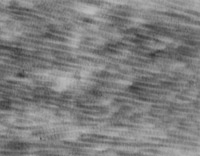

经MEBT/MEBO治疗20天,电镜观察到基底细胞层与纤维母细胞之间的半桥粒连接,同时可见纤维母细胞内粗面内质网结构和线粒体增生活跃(图5-3-19~5-3-21)。 MEBT/MEBO治疗30天后,上皮组织再生修复,已基本完成,创面组织切片显示胶原纤维成熟,排列整齐(图5-3-22),直径为0.1~0.5祄,并可见明暗相间周期性横纹(64nm),未见到胶原纤维扭曲和呈旋涡、菜花等病理形态。

5-3-22 MEBT/MEBO治疗30天,整齐排列的胶原纤维,纤维均匀一致直 径 0.1~0.5祄,有明暗相间的周期性横纹(64nm)